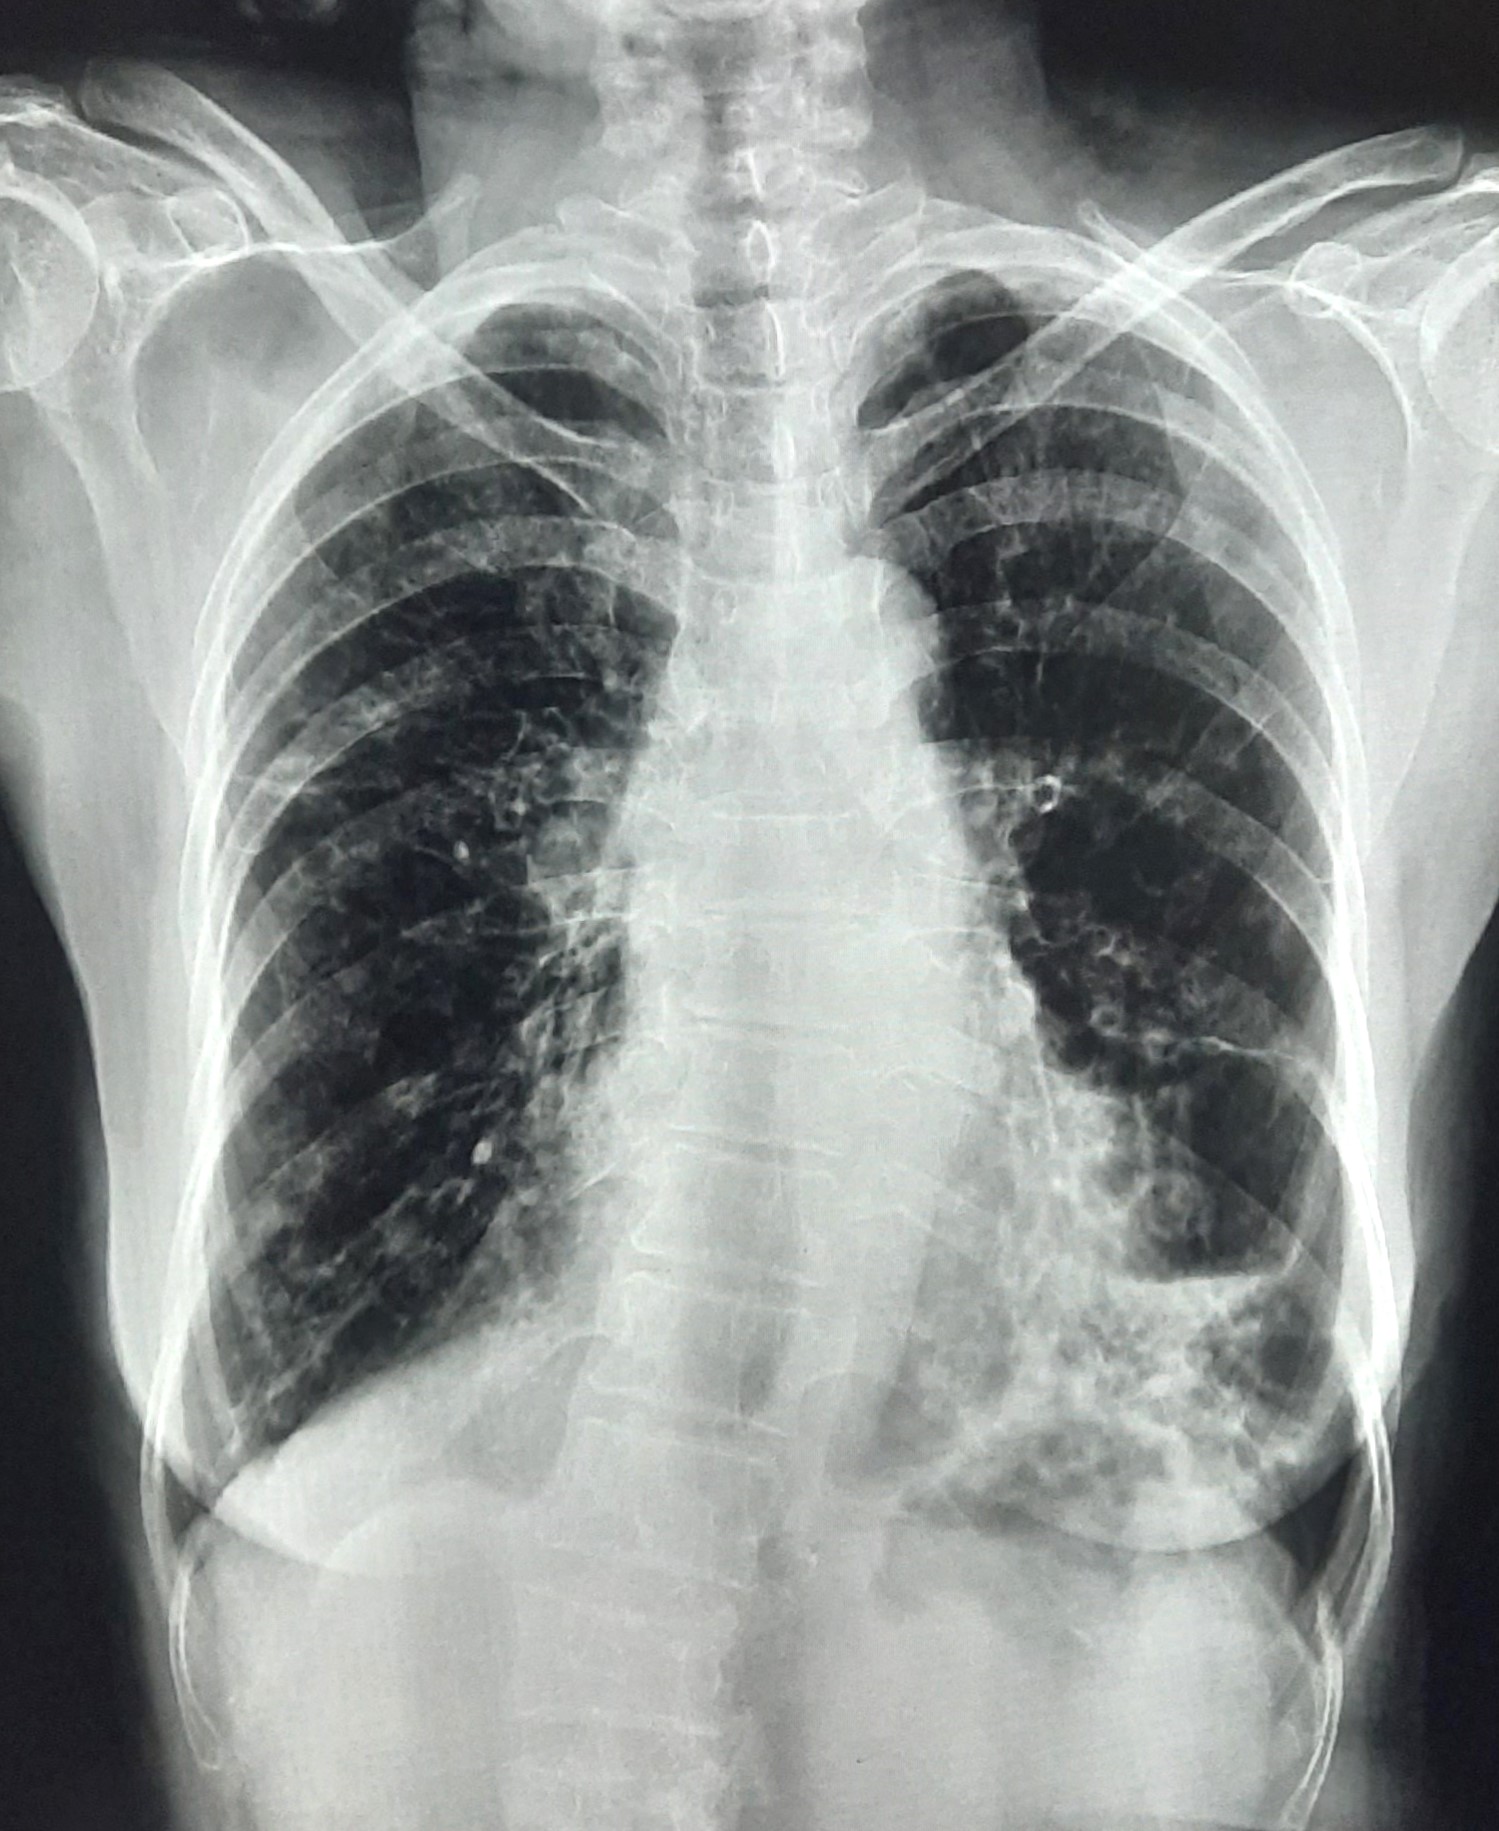

| 152 | IGGMC, Nagpur, Nagpur | P2 | 29-4320 | Dewakabai Thakare | Consent taken on Paper | 80 Yrs. |

Provisional Diag : Post TB Sequel

Final Diag : Post TB sequelae with emphysematous Hyperlucency |

Post TB Sequelae | Left Lower Zone Ill Defined Opacities Present With Hyperlucency Left Lower Zone | Abnormality visible on x-ray |